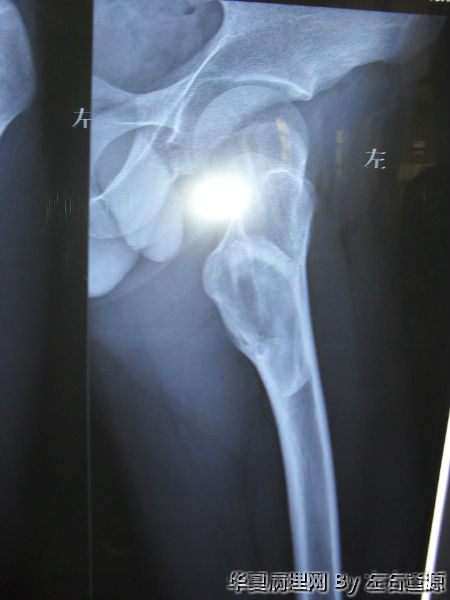

男19岁 左股骨上段异常增殖

• 男19岁 左股骨上段异常增殖图1

图1